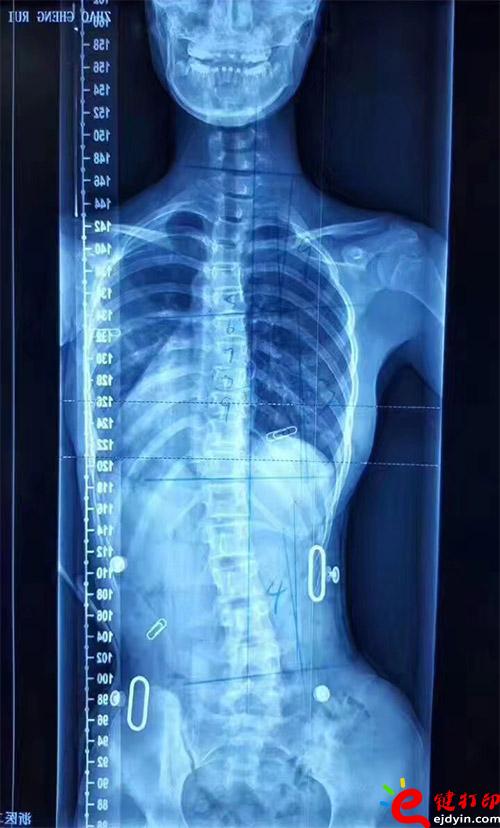

在脊柱側(cè)彎患者中,僅有10%的青少年特發(fā)性脊柱側(cè)彎患者最終需要手術(shù)治療,90%的患者可以保守治療和積極觀察。非手術(shù)治療中公認(rèn)最主要和可靠的方式是用矯形支具治療。像上圖這樣的案例就可以通過矯形器治療。每個人的畸形不一樣,就需要像3D打印這樣可定制又便宜的技術(shù)幫助。